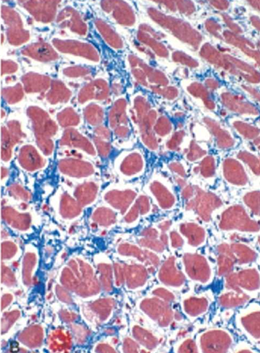

Dilated Cardiomyopathy

Myocyte hypertrophy and interstitial fibrosis (Blue with masson trichrome stain)